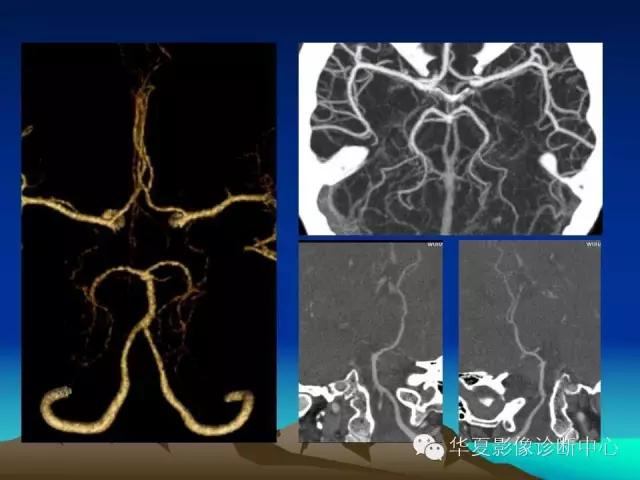

你不知道的脑血管解剖都在这里!